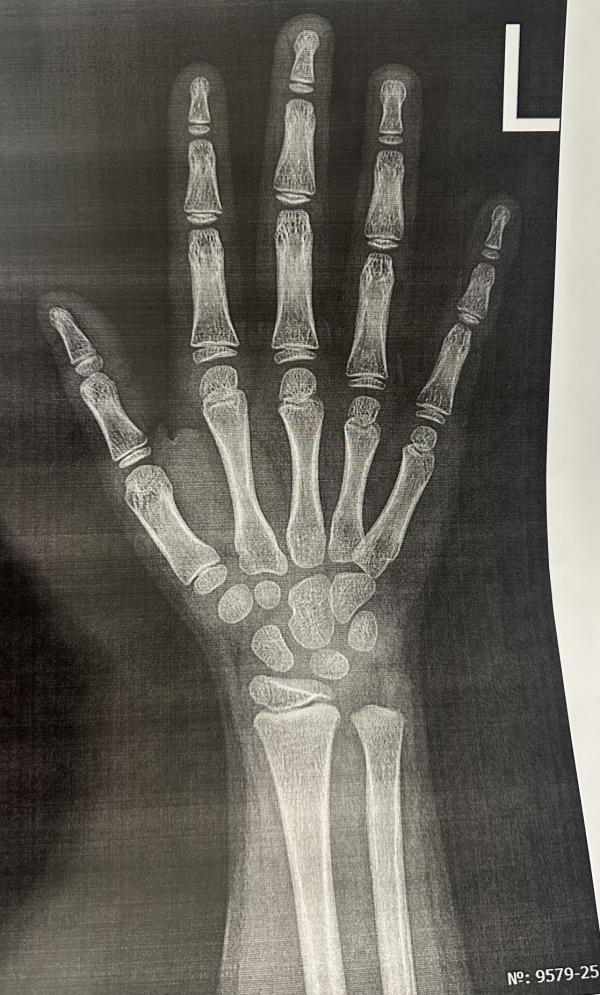

Точно такая же как у моей дочери. 6 лет. Сказали точно по паспортному возрасту.

На вашем фото и что девушка скинула, косточки лежат как на фото 7 лет, точь в точь.

Предполажу, что костный возраст до 7 лет, т.к. нет дистального эпифиза локтевой кости. У меня старшая каждый год делает снимки кисти.